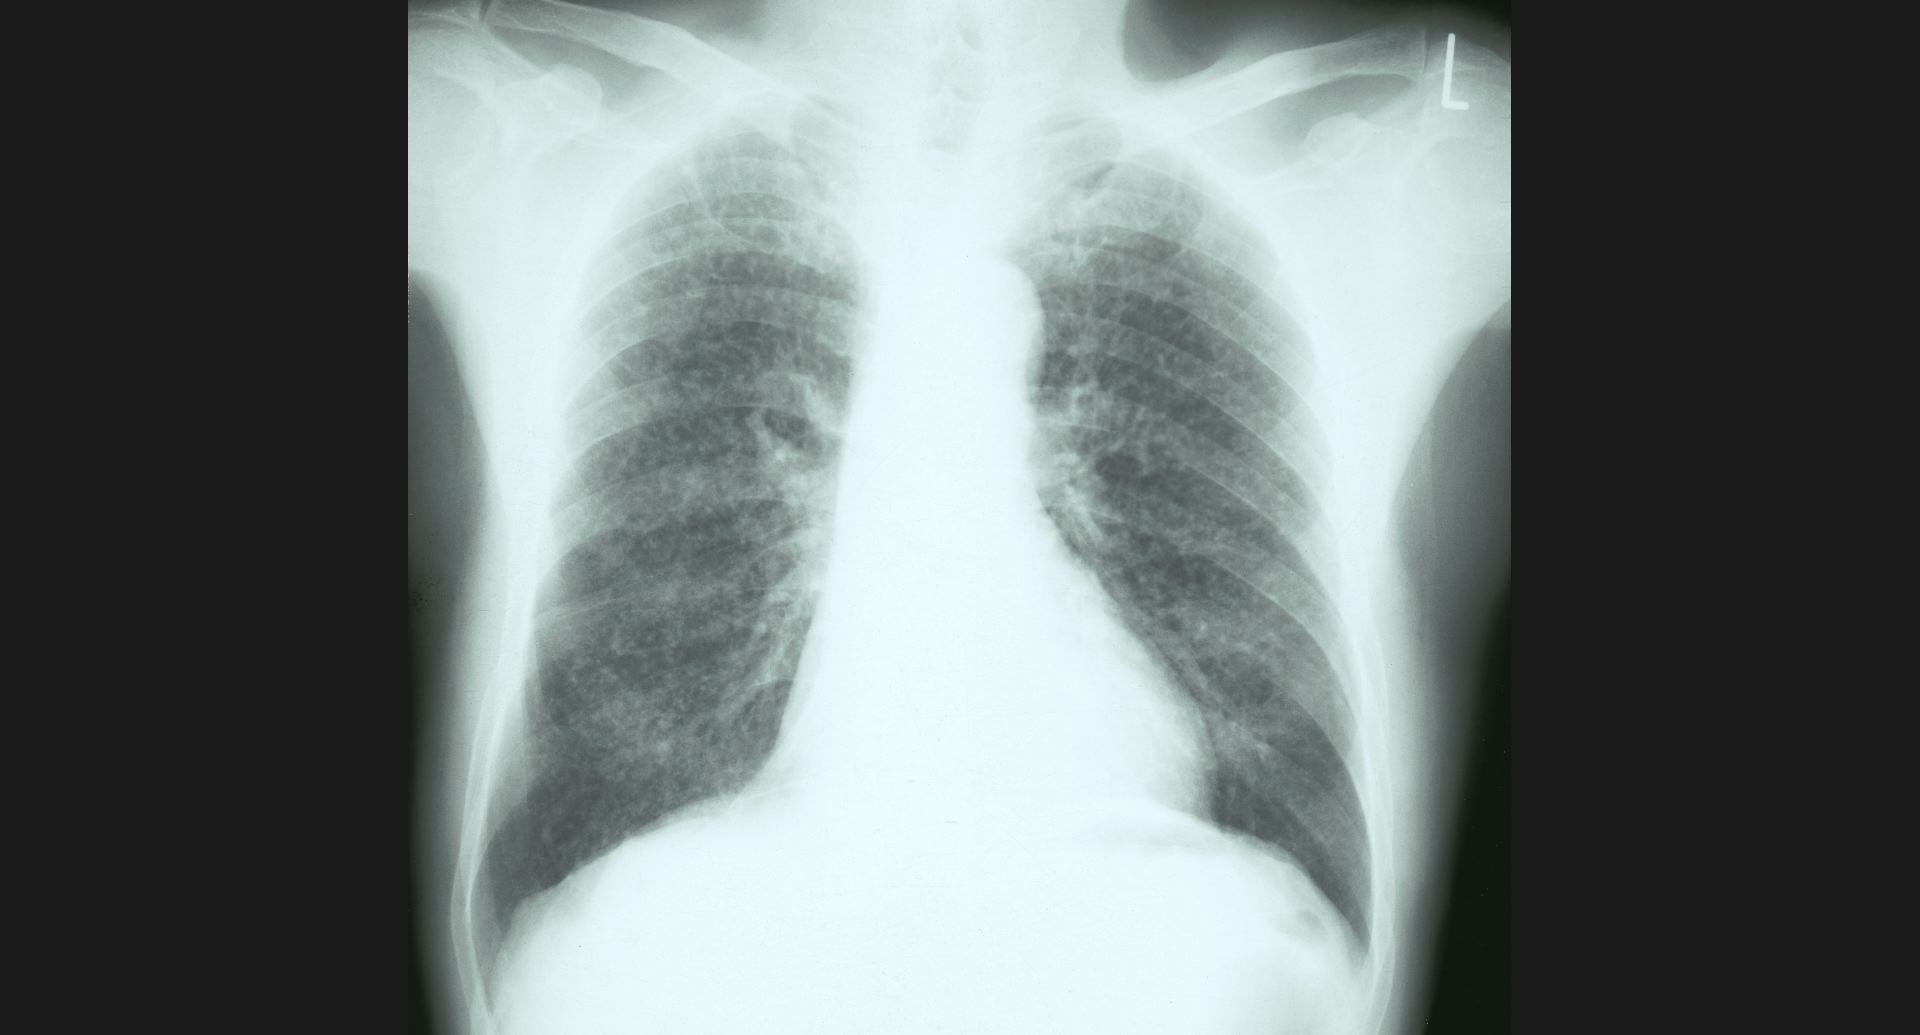

fig.6(97KB) :Alveolar proteinosis (tomography)

butterfly pattern, air bronchogram。